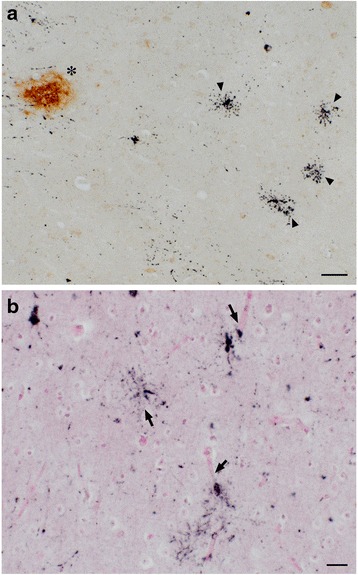

Oligodendroglia-like cells in the hippocampal white matter were identified on AT8/DAB stained sections embedded in Epon and trimmed for electron microscopic examination (Fig. 6a). In these cells, non-twisted filaments with a diameter of 20–25 nm were randomly scattered with occasional parallel streams in the cytoplasm (Fig. 6b, inset). Because ultrastructures and DAB labeling are both electron-dense, distinguishing between DAB labeled structures and ultrastructures is difficult. To address this problem, we first immunolabeled with DAB in the presence of ammonium nickel sulfate, so that DAB precipitates contained nickel. We next analyzed sections using STEM and energy dispersive X-ray (EDX) analysis to identify Ni-specific energy peaks (Fig. 6a, compare area c, Ni+, with area d, Ni-). By plotting the presence or absence of Ni in each pixel in the EM field, we were able to accurately map tau IR. We further show that the distribution of Ni (Fig. 6e Ni, purple) is distinct from the distribution of components of non-specific electron dense regions, including osmium (Fig. 6f Os, cyan), lead (Fig. 6g Pb, red) or uranium (Fig. 6h U, green).

When we analyzed neurons using this technique, we found similar electron-dense labeling in the neuronal cytoplasm, sometimes in close contact with the outer nuclear membrane (Fig. 7). Solid filamentous structures, as seen in oligodendroglia-like cells, were present, but rare in neurons (Fig. 7 inset, arrowheads). The scarcity of filamentous structures in neurons may be correlated with less intense argyrophilia on Gallyas silver impregnation (Fig. 2c).

EDX isolation of DAB-Ni labeling from the background

In our previous studies [ref. 20], we distinguished between electron-dense areas due to immunolabeling from background electron-dense areas by labeling with Quantum dot nanocrystal (QD). This EDX detection of the QD constituents, selenium and cadmium, was further extended to map these elements by highlighting against background structures (EDX mapping) [ref. 9]. In our current study, we developed a novel technique of immunoelectron microscopy (immuno EM) by applying this EDX mapping on ultrathin sections, developed with DAB enhanced with nickel ammonium sulfate. Because EDX spectra can detect the presence of nickel in DAB decorated areas (Fig. 6a, area c, Ni+), and because nickel is not found in background areas (Fig. 6a, area d, Ni-), it was possible to map pixels containing nickel over the entire EDX field (Fig. 6e, Ni, violet) to identify specific DAB-positive regions. Similar maps for peaks of osmium (Fig. 6f, Os, cyan), lead (Fig. 6g, Pb, red) and uranium (Fig. 6h, U, green) identified background electron-dense regions that were qualitatively different from the Ni-specific maps. This approach, easily performed by analyzing DAB-Ni decorated sections with EDX, may greatly expand the utility and reliability of DAB-Ni decorated EM preparations by distinguishing specific signals from otherwise indistinguishable backgrounds of similar electron density.

PSP-like ultrastructure of tau filaments in oligodendroglia-like cells

4R tau labeling and Gallyas argyrophilia were more intense in oligodendroglia-like cells in the white matter (Fig. 4b) than in neurons (Fig. 2c). In these oligodendroglia-like cells, AT8-labeled fibrils were 20–25 nm in diameter without apparent constriction (Fig. 6b), similar to those reported in tau-positive fibrils in oligodendroglia in PSP brains [ref. 27]. In contrast, in oligodendrotcytes in AD brains, mixtures of straight filaments with a diameter of 16 nm, and irregularly constricted filaments with greatest width of 30 nm have been described [ref. 28].

In our study, neurons in aged monkeys were positive, specifically for 4R tau, but argyrophilia with Gallyas was much less intense, suggesting an early, premature state of tau deposition, and aggregation as pretangle neurons. It was possible to identify some AT8-decorated fibrils in the neuronal cytoplasm (Fig. 7 inset, arrowheads), but these were much less abundant than in oligodendrocytes, and their random arrangement without forming PHFs resembles pretangle neurons in CBD [ref. 9].